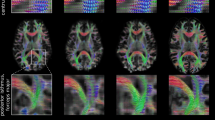

Figure 4 shows example output images of CycleGAN and SFCGAN. The coronal cross-section in the figure is obtained by stacking elements from axial slices. The axial-coronal slice pairs are taken from different patients and correspond to different pelvis segments for diverse visual inspection.

MR to CT conversion. In the above figure, column (i) represents ground truth MR (ii) represents ground truth CT . In column (iii) and (iv), the black background images are synthesized CT by CycleGAN (baseline) and SFCGAN respectively. The images in the white background represents the corresponding error in synthesized CT.

Figure 4 shows the output generated by SFCGAN. It can be seen that differences in the intensity values of soft tissues in original CT and sCT is minimal. Although sCT has brighter pixels at the edges compared to the CT, there is a considerable difference in intensity values at the bone and soft tissue boundaries. Additionally, incorporating optical flow information as an input enables our model to maintain the interframe consistency in sCT. The interframe consistency is reflected in the continuity of bones and tissues along the vertical axis in the coronal cross-section of SFCGAN results. Unsurprisingly, the same is absent in CycleGAN.